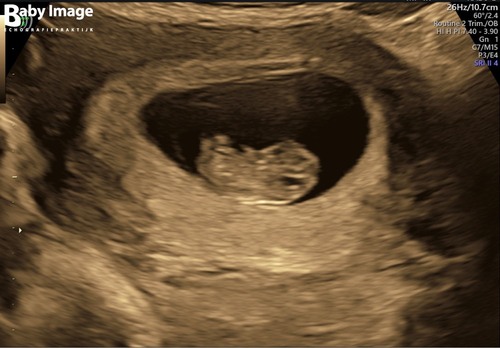

Deze was rond 8+4. Vroeger dan de vorige foto maar scherper beeld door ander echo apparaat!